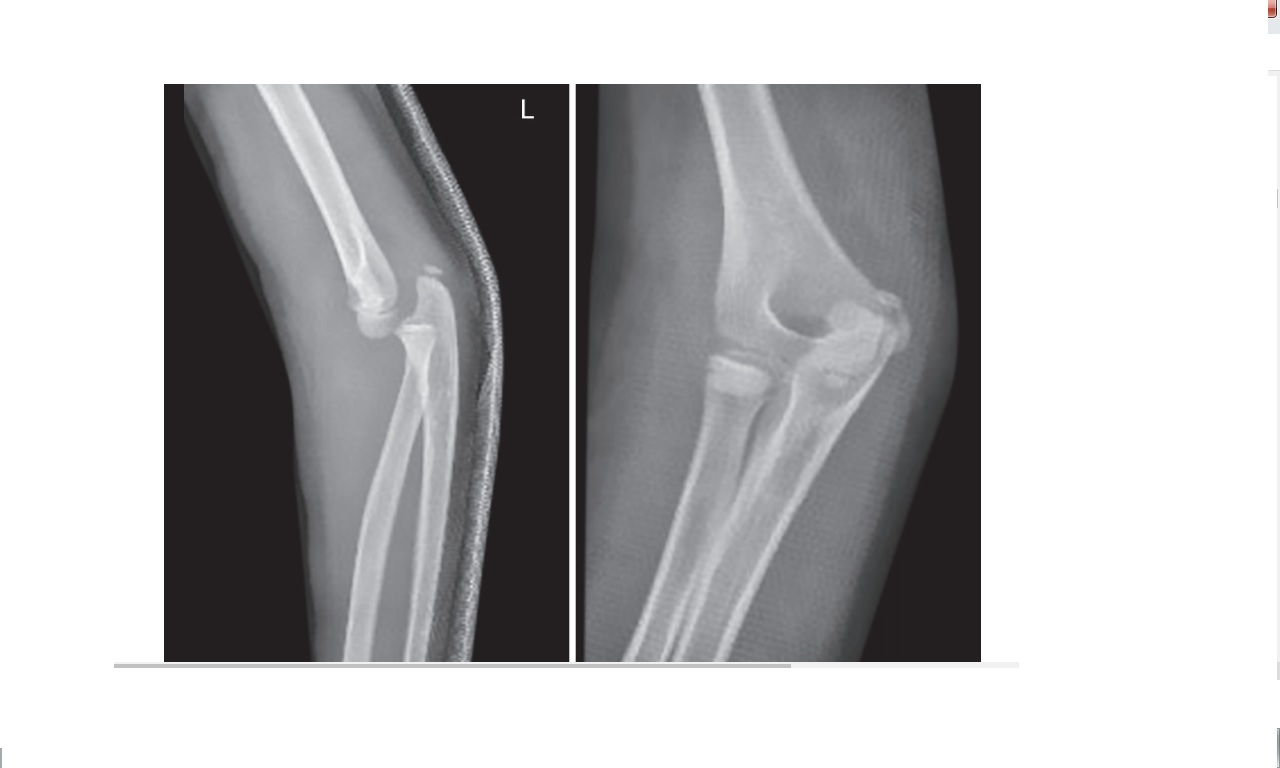

- The Enigmatic Elbow and TRASH Lesions

Courtesy: Sandeep Patwardhan, Ashok Shyam, Sancheti Institute, Pune and IORG, OrthoTV